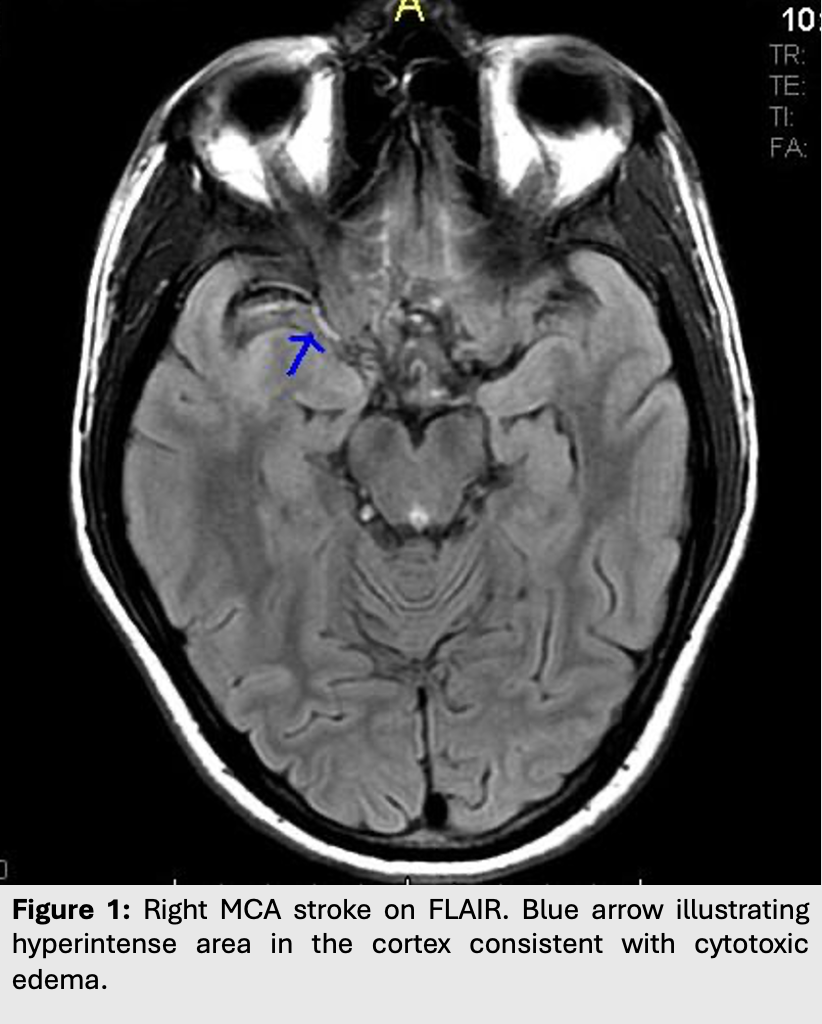

Figure 1: Right MCA stroke on FLAIR. Blue arrow illustrating hyperintense area in the cortex consistent with cytotoxic edema.

• Cortical edema takes at least 3 hours before it can be seen on T2/FLAIR (hyperintense with cortical thickening and loss of grey-white junction differentiation).

• However, it only takes between 10 to 60 minutes for and acute MCA infarct to be seen on DWI.